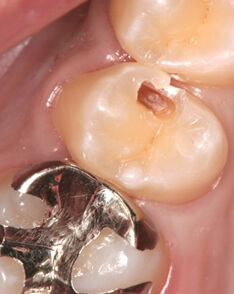

ダイレクトボンディング症例4

虫歯が進行した部分のみを除去

術前

患者さんはダイレクトボンディング法を希望されたため虫歯が進行した部分のみを除去しました(削る量は最小限で済むため歯にやさしい治療です)